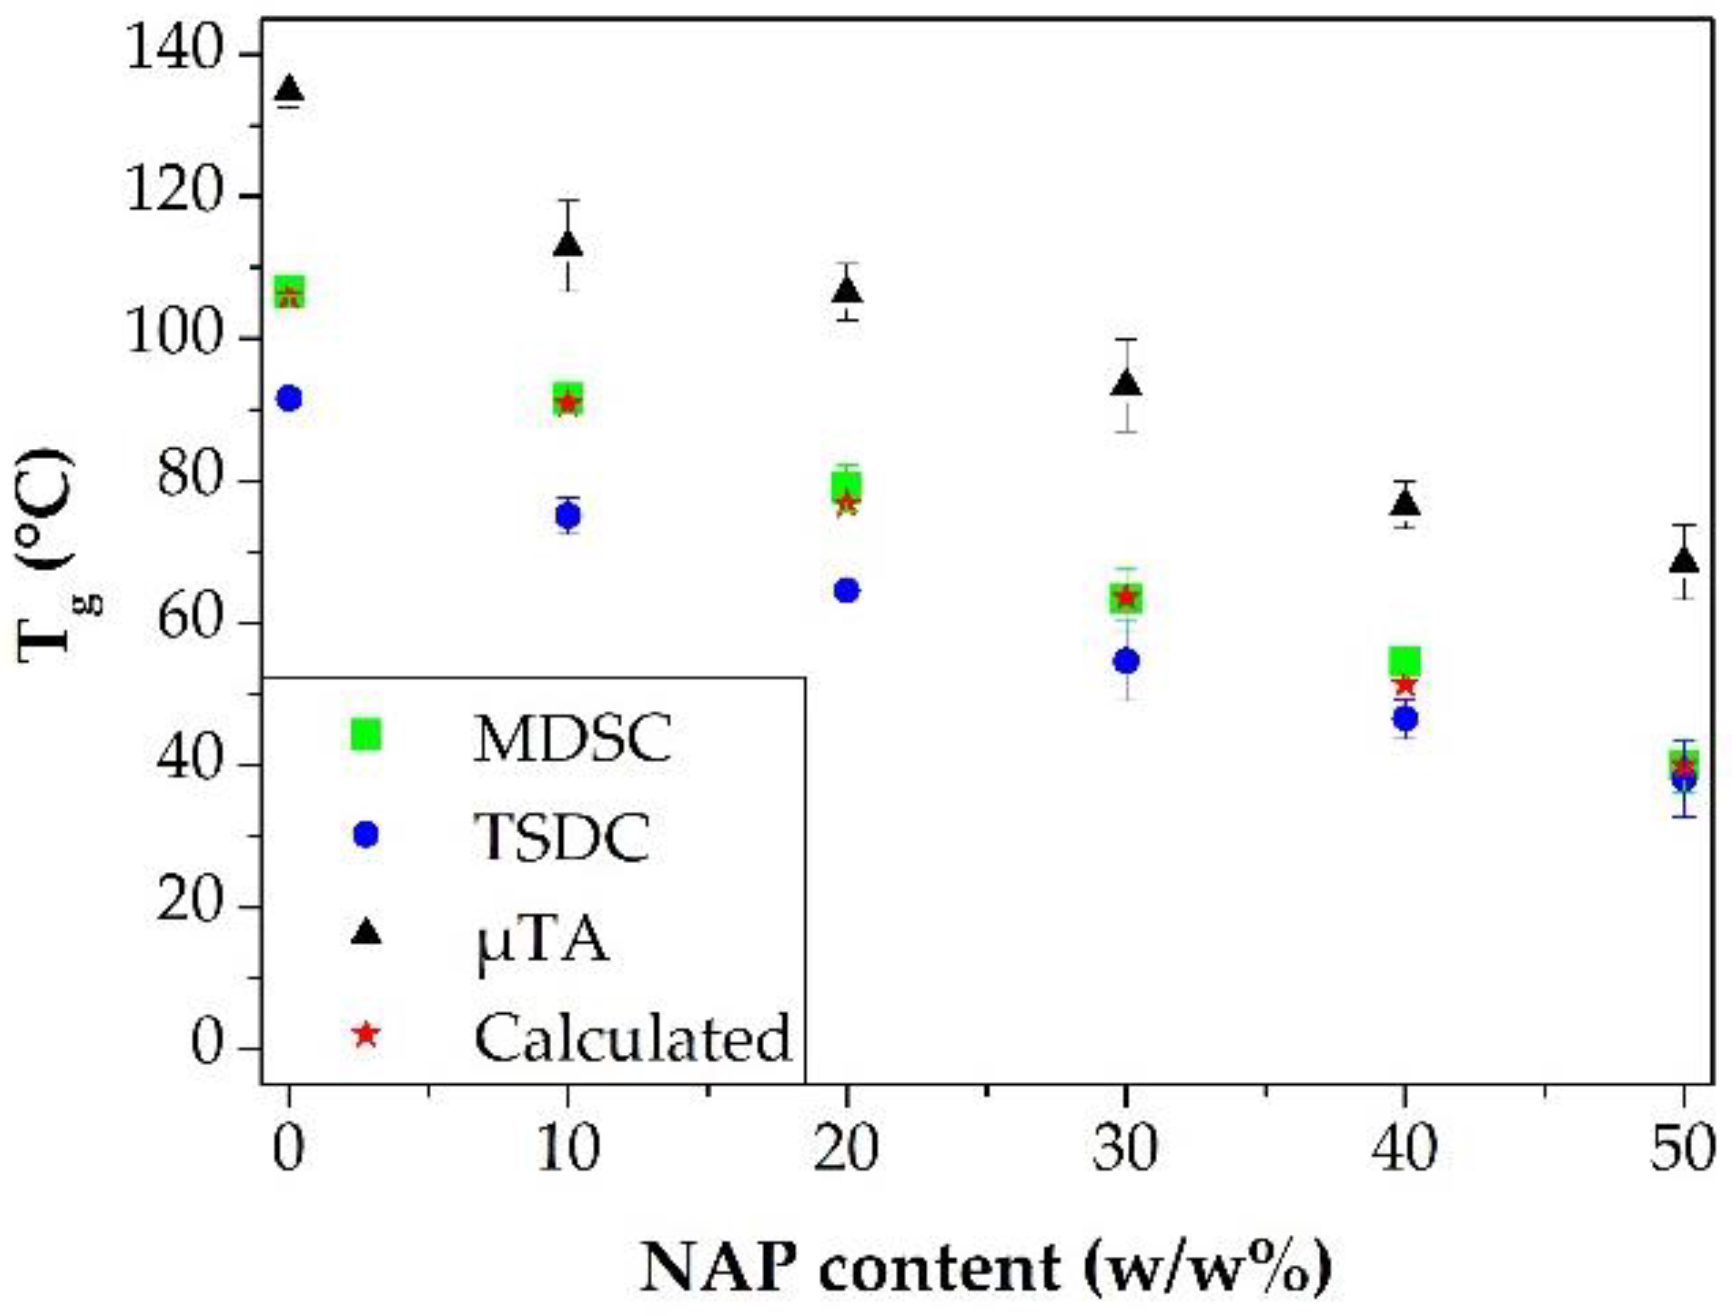

3.2. Measuring the Glass Transition Temperature with Different Methods

3.4. Correlations between the Measured Tg Values and the Stability